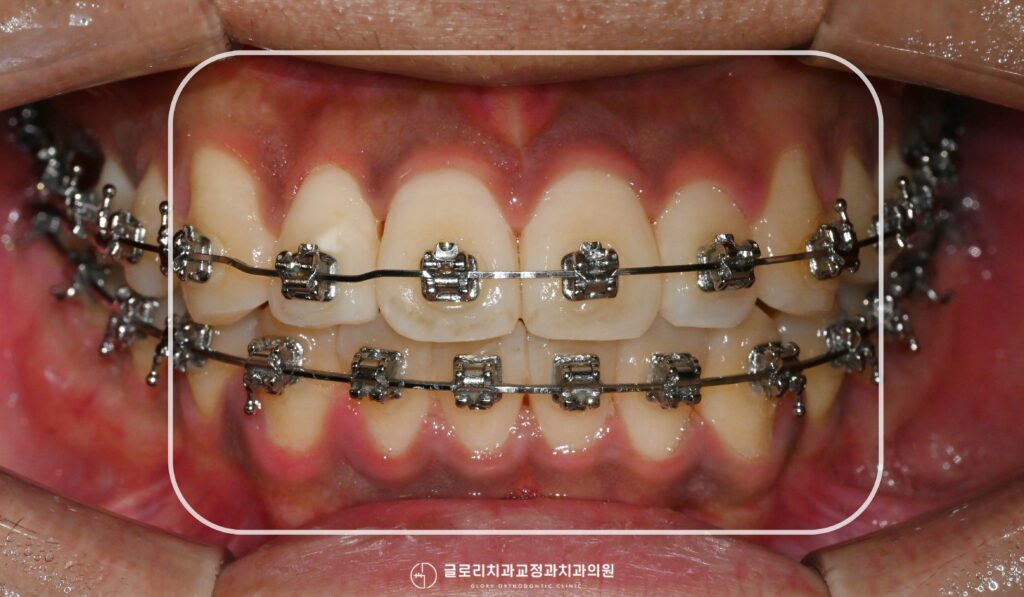

상봉동 교정치과 에서 준비한 사진을 보면 현재 전치부가 겹치고

틀어진 총생이 뚜렷하게 확인됩니다. 개별 치아가 제 위치를 벗어나

앞뒤로 어긋나 있으며 고르게 배열되지 못한 형태이죠.

또한 정중선이 좌측으로 편위되어 위아래 치열의 중심선이

일치하지 않는 것을 확인할 수 있는데 정중선의 편위는 교합 시

좌우 균형이 맞지 않아 특정 부위에 하중이 집중될 수 있어 기능적인 측면에서도 개선이 필요합니다.

현재 상악 측절치는 안쪽으로 심하게 회전되어 인접치와의 공간이

거의 확보되지 않은 상태인데 전체적으로 치열궁의 폭이 좁고 공간이 부족하다 판단됩니다.

본격적인 교정이 이루어지며 서서히 치아가 계획된 위치로 이동합니다.

확보된 공간을 바탕으로 겹쳐있던 전치부가 하나씩 자리를 잡아가며 전체 배열이 완성될 수 있죠.

이번 케이스에서 또 한가지 중요하게 다뤄진 부분이 바로 안쪽으로 심하게 회전되어있던 상악 측절치였는데요.

브라켓을 통해 회전력을 지속적으로 가해 치아를 올바른 방향으로 천천히 돌리는

과정이 필요합니다. 따라서 전치부 공간이 확보되었다면 설면에 버튼을 부착한 뒤

고무줄과 브라켓의 협측힘을 동시에 활용해 치아 양쪽에서 회전력을 가하는 방식으로 접근하게 됩니다.

설면의 버튼은 치아 안쪽면에 부착하는 작은 보조장치로 브라켓만으로는 조절이 어려운

회전 이동을 보다 효과적으로 다룰 수 있게 해줍니다.

상봉동 교정치과 에서 준비한 자료를 보면 초진 시 안쪽으로 돌아가있던 전치부가

올바른 방향으로 되돌아오면서 인접치와 가지런히 배열된 것을 확인할 수 있습니다.